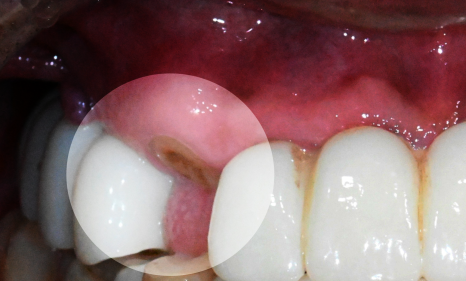

오늘은 치아머리 부분 즉, 치관이 온전히 부러진 경우

어떤 치료가 필요한지 설명해 드리려 합니다.

앞니 치관 파절

사진을 보시면 우측 윗쪽 앞니의

머리 부분이 온전히 부러졌습니다.

잇몸을 절개하여 치아머리 부분을 확보하는 시술로

지금처럼 파절된 범위가 넓을 때 적용해 볼 수 있으며,

본래 치아가 작고 길이가 짧아 뭉툭한 인상을 줄 때

심미를 개선하기 위해 사용하기도 합니다.

예전에는 외과적으로 절개하는 방식을 주로 사용했으나,

출혈이 생겨나며 치유 기간이 다소 길어

최근에는 레이저를 활발하게 사용하고 있습니다.

레이저를 사용하여 출혈량을 줄이고

회복 기간을 확연히 단축시킬 수 있습니다.